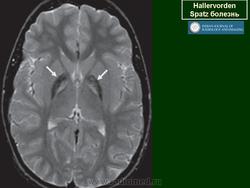

Галлервордена - Шпатца болезнь (J. Hallervorden, 1882-1965, нем. невропатолог; H. Spatz, совр. нем. невропатолог; син. ригидность прогрессирующая) - наследственная болезнь, связанная с нарушением обмена железа и липидов, проявляющаяся в возрасте 7-9 лет повышением мышечного тонуса, гиперкинезами, прогрессирующей деменцией, снижением зрения и пигментным ретинитом; наследуется по аутосомно-рецессивному типу.

Болезнь Галлервордена - Шпатца - наследственное заболевание экстрапирамидной системы, связанная с нарушением обмена железа и липидов и повреждением бледного шара и черной субстанции. Тип наследования аутосомно-рецессивный. При патоморфологическом исследовании характерным признаком является гиперпигментация бледного шара и черной субстанции. Обнаруживается пигментация коры полушарий большого мозга и таламуса. Пигмент находится внутри невронов и глиальных клеток, расположенных около сосудов; содержит железо (вместе с тем каких-либо нарушений обмена железа в организме не обнаружено). Наблюдаются утолщение и фрагментация аксонцилиндров в пораженных областях. Постепенно наступает дегенерация невронов коры полушарий большого мозга и мозжечка. Характеризуются нарастающей экстрапирамидной ригидностью, гиперкинезами (атетоз, торсионная дистония), затем развивается акинетико-ригидный синдром, пирамидная микросимптоматика, снижение интеллекта. Течение медленно прогрессирующее на протяжении 10 - 20 лет.

"Глаз тигра"-наглядно и красиво.